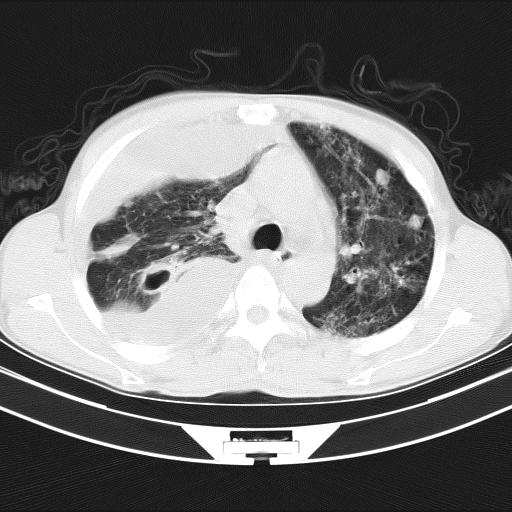

男性,44岁,结核病史多年。现胸闷气短,咳嗽,偶咳血。

右侧胸腔积液

右肺下叶不张

双肺多发结节影最分空洞形成考虑占位不除外结核

双肺陈旧性病变

1、右侧大量胸腔积液伴右肺压缩性膨胀不全,建议抽液治疗后复查 2、两肺继发性tb伴空洞形成。

1)两肺继发性肺结核伴空洞形成,左肺多发性结核球。2)右侧大量胸腔积液伴右肺部分膨胀不全。3)纵隔淋巴结肿大。

1,双肺多发结节 并空洞影改变, 左侧胸腔积液并部分包裹, 结合原病史首先考虑结核. 但也不除外其它.

2,左侧有一根肋骨陈旧性骨折? 建议追查 .